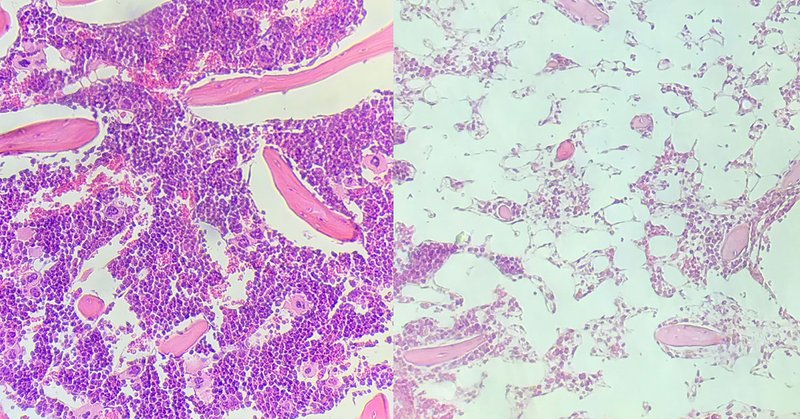

#CARTcell targeting CD7 could significantly decrease a patient’s immune function. Our recent preclinical work led by Dr. Miriam Kim shows that a transplant of hematopoietic stem cells with CD7 #CRISPR’d out could solve that problem. https://t.co/9CTZ3VAcpF